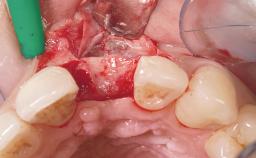

A 36-year-old female patient was referred for the replacement of the upper left central incisor (tooth 21), which had fractured. Although the tooth had been asymptomatic for many years, the crown began to loosen, at which time she presented to her dentist for an assessment. Teeth 21 and 22 had both been endodontically treated many years previously. She was a healthy individual and a non-smoker.

The crown of tooth 21 was splinted to the adjacent teeth with composite resin, and the gingiva was inflamed.